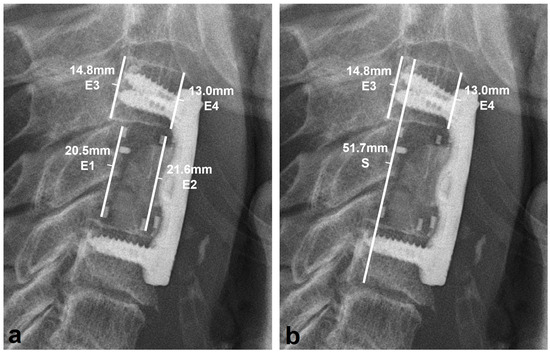

3.2. Radiologic Outcomes